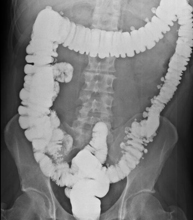

- Enema opaco

Prueba diagnóstica que consiste en obtener imágenes radiológicas del intestino grueso (colon y recto) mediante el empleo de rayos X y de un contraste opaco que se administra a través del recto, en forma de enema.

- Enema opaco doble contraste

Prueba diagnóstica que consiste en obtener imágenes radiológicas del intestino grueso (colon y recto) mediante el empleo de rayos X. Se utiliza un contraste opaco que se administra a través del recto, en forma de enema y, también, se introduce aire para expandir el colon.